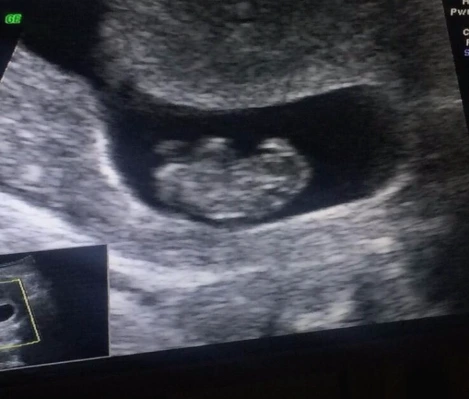

드디어 만나러 가는 날. 젤리곰 반가워!!

남편이나 나나 아직은 중국어가 많이 서툴기에 통역사와 함께 상담실/초음파실/진료실을 차례대로 다니며 검사했다. 초음파로 확인한 우리 아가는 이제 막 2.3cm 9주가 되었단다. 어머 손가락 한마디 정도 되는 건가..? 그런데 심장/머리/팔/다리/뇌 등등 다 있다니! 진짜 사이즈며 겉모습도 젤리곰 같아 너무 신기했다. 심장 뛰는 소리 대신 혈액이 흐르고 있는 것으로 건강히 잘 크고 있음을 확인했다. 심장소리 듣고 싶었는데 아직 초반이라 아가에게 스트레스 갈 수 있다고 12주 진료 때 들려주겠단다. 직접 소리를 들어야 마음이 더 편할 듯 하지만, 큰 특이사항 없는 한 아가한테 자극을 많이 안 주는 게 좋은 것 같기도 해서 병원의 조언대로 기다리기로 했다 :)

처음엔 머리가 오른쪽인가..? 했는데 볼 수록 왼쪽이 머리인 듯. 어렵다.

드디어 너의 존재를 눈으로 확인했어. 봐도 잘 모르는 사진이지만 보고 또 보고. 다른 것 보다 건강히 잘 크고 있다는 한 마디에 참 감사했어.